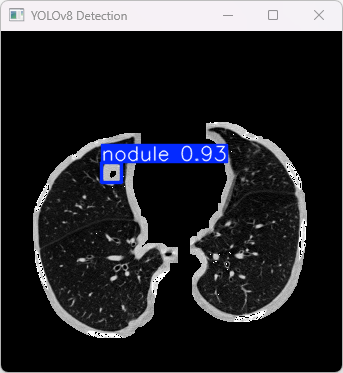

4.检测结果识别

模型训练完成后,我们可以得到一个最佳的训练结果模型best.pt文件,在runs/train/weights目录下。我们可以使用该文件进行后续的推理检测。

imgTest.py 图片检测代码如下:

此代码的功能是加载一个预训练的YOLOv8模型,对指定的图片进行目标检测,并将检测结果显示出来。

执行imgTest.py代码后,会将执行的结果直接标注在图片上,结果如下:

这段输出是基于YOLOv8模型对图片“image.jpg”进行检测的结果,具体内容如下:

图像信息:

(1)处理的图像路径为:E:\PulmonaryNodulesDetection_v8\TestFiles\0229.png。

(2)图像尺寸为 640×640 像素。

检测结果:

(1)模型检测到 1个结节 (nodule)。

(2)每张图片的推理时间为9.2毫秒。

处理速度:

(1)预处理时间:5.283 毫秒

(2)推理时间:9.213 毫秒

(3)后处理时间:99.137 毫秒

检测类别:

YOLOv8模型检测的1类病变:

(1)1 个结节 (nodule)

此YOLOv8模型检测出了图像中的1个结节,整个处理流程包括预处理、推理和后处理,总体运行速度较快,结果被保存到指定的文件夹。